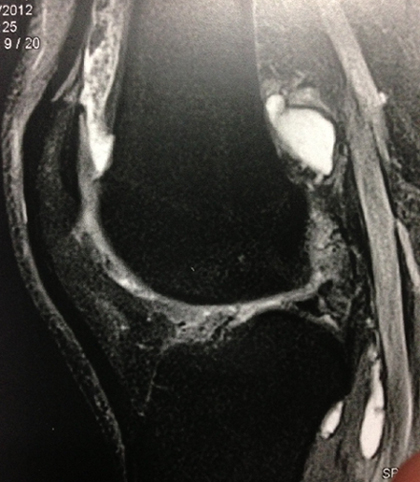

Cas clinique N°50

Dr Véra Lemaire Paris

Un cas clinique facile pour Noël :

il s'agit d'une jeune femme âgée de 26 ans qui consulte pour un gonflement modéré et intermittent du genou droit.

L'examen clinique est normal par ailleurs ; les radiographies sont normales.

Une IRM est faite.

Qu'en pensez-vous ? Que conseillez-vous ?